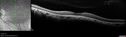

Sectoral Retinitis Pigmentosa - Asymptomatic258 views56-year-old female - The patient was in for an annual checkup because of her diabetes. No visual complaints (no night vision trouble)

293 Invitae genetic panel - negative     (0 votes)